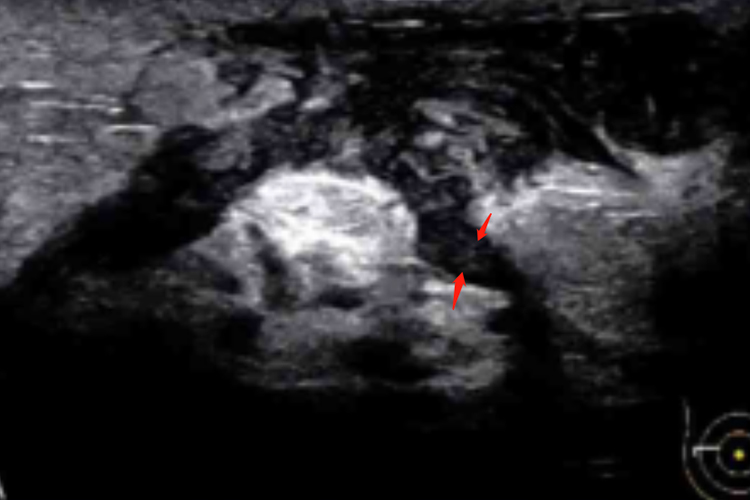

Ⅳ型:腺体层内见部分或完全性液化的脓肿样回声,边界不清晰,液化区可见细小流动感低回声,部分病例可见瘘管样回声。